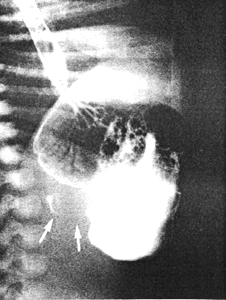

Case 23.2. B.B., 28 day old male, had a history of post-feeds vomiting for the previous 2 weeks. Radiographic examination showed a severe, constant narrowing 2.0cm in length in the pyloric region of the stomach, causing obstruction. The narrowing was string-like in appearance and at its proximal end associated with concave indentations into the stomach (Fig. 23.3). The appearance is compatible with IHPS and can be explained as follows: hypertrophy of the musculature of the entire length of the pyloric sphincteric cylinder causes a pronounced narrowing of the lumen, which is permanent. Muscular hypertrophy surrounding the narrowed lumen indents the stomach, causing concave defects. The diagnosis of IHPS was confirmed at operation.

| Fig. 23.3. Case B.B. String-like narrowing 2.0cm in length (arrows) due to pyloric muscular hypertrophy |